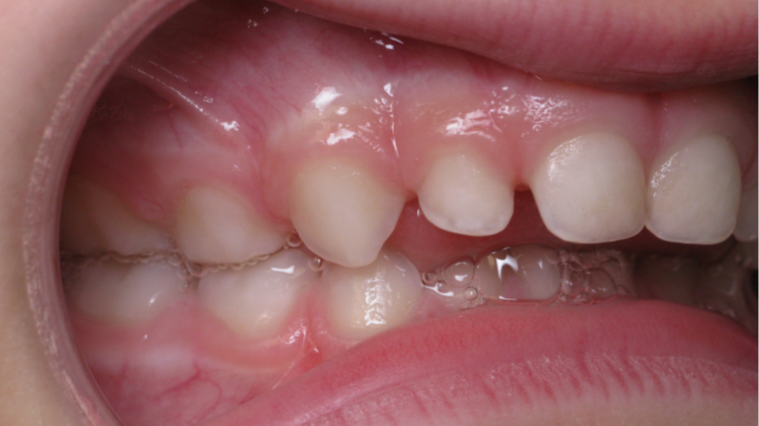

surveillance évolution de la dentition pendant 4 ans

bilan début fin de traitement